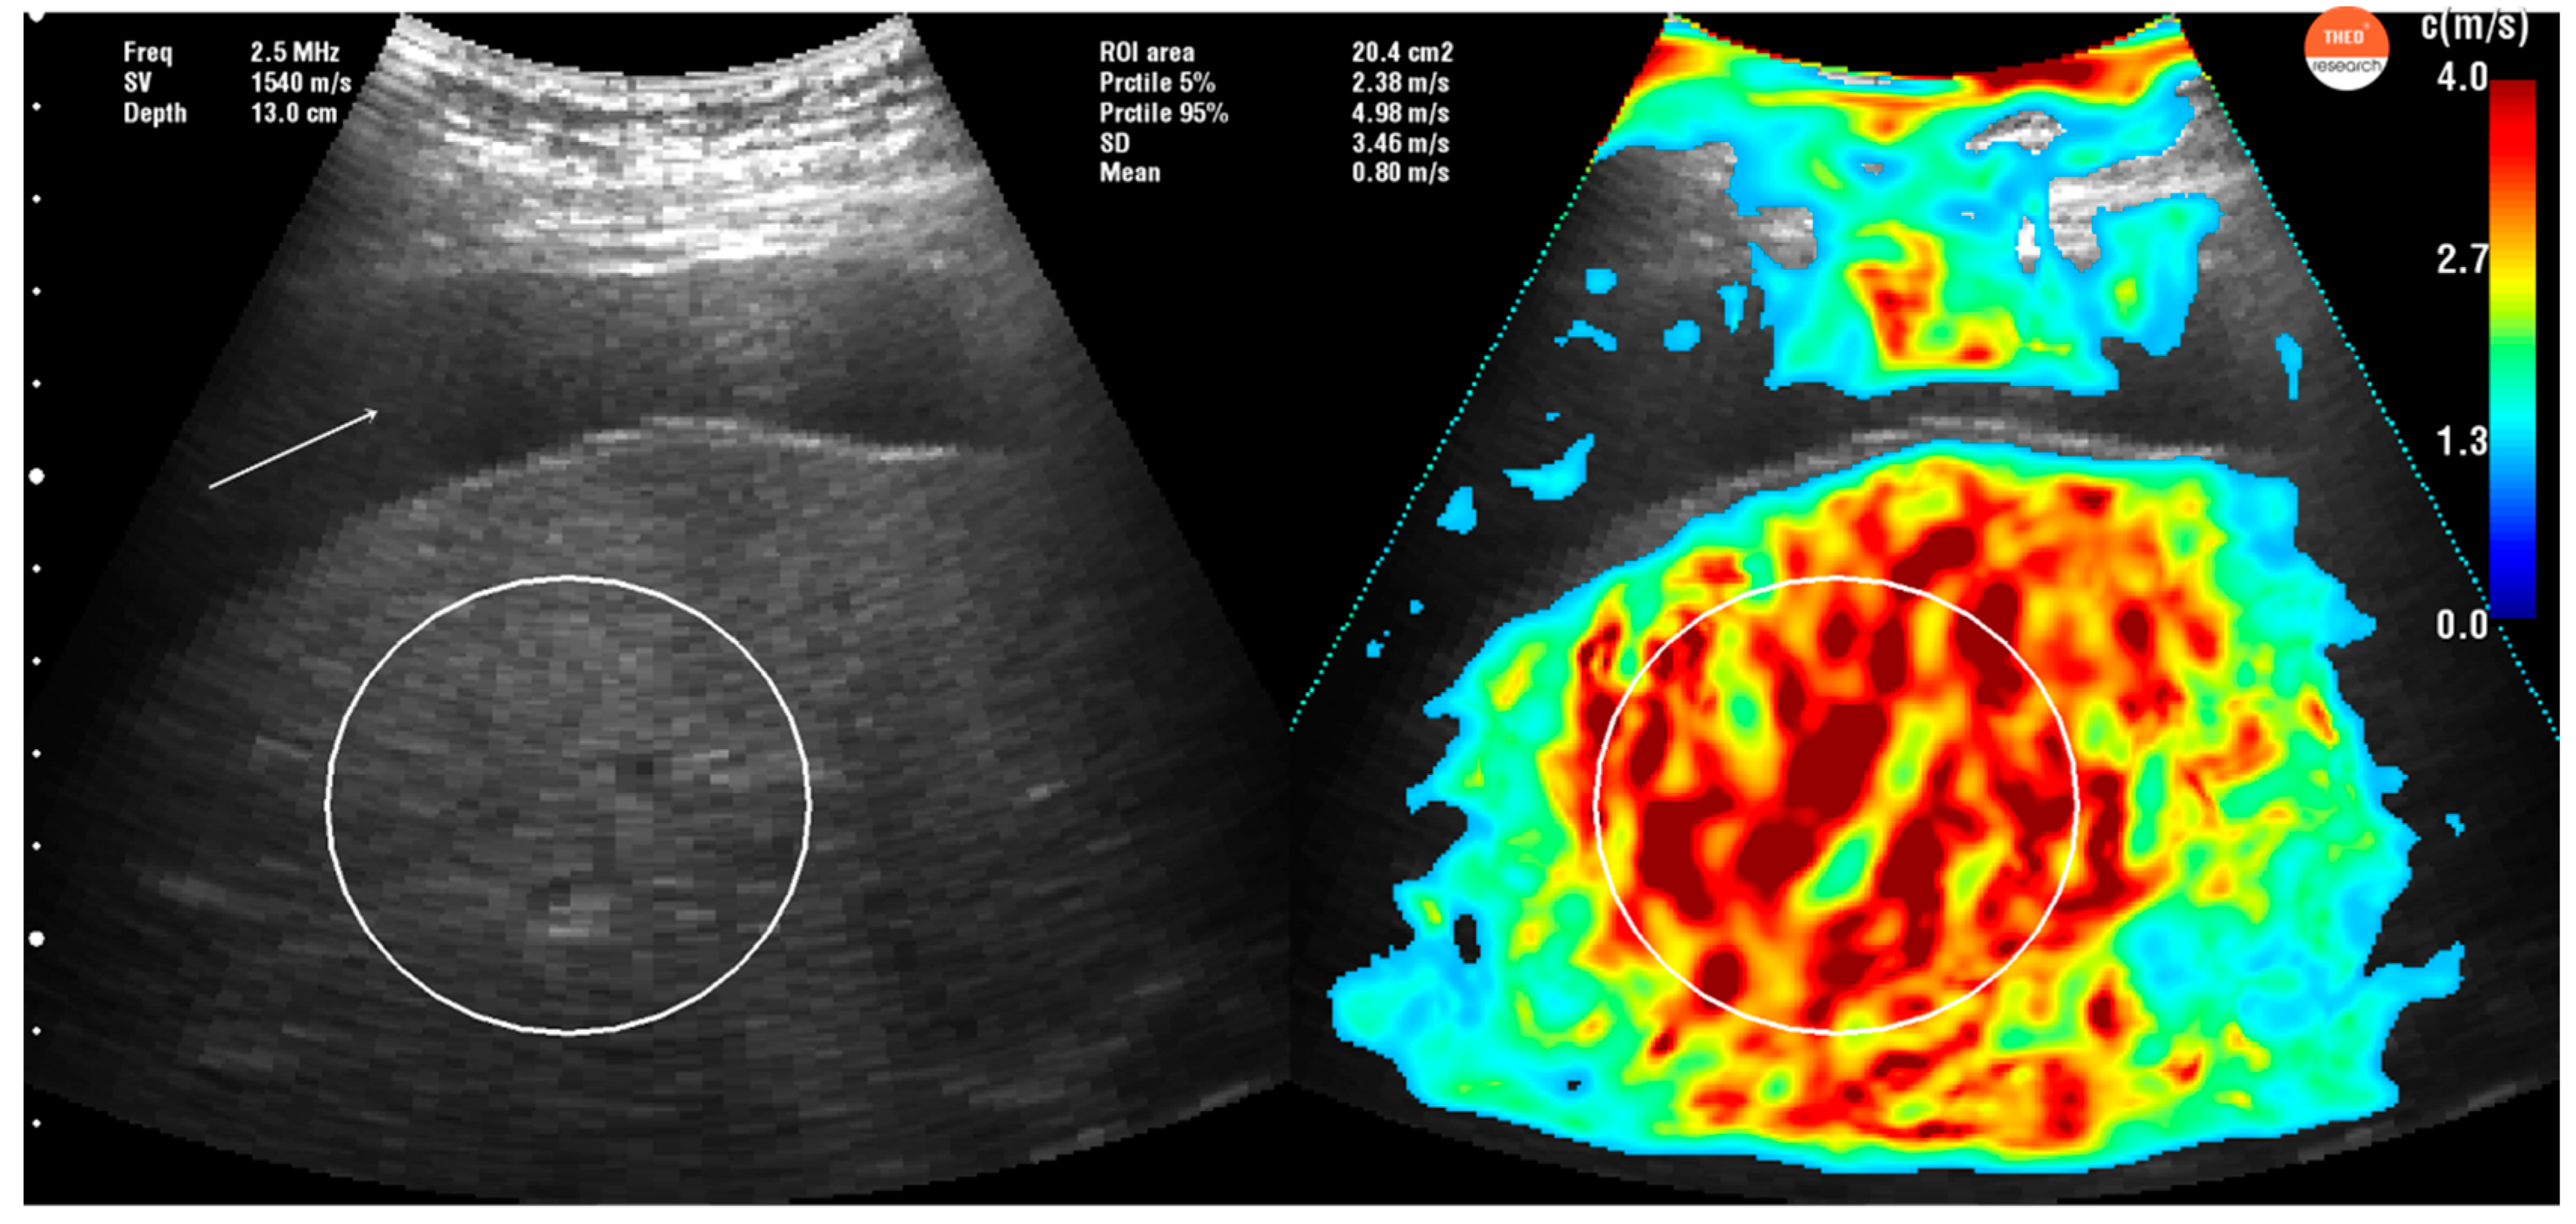

2.3. Time Harmonic Elastography Evaluation